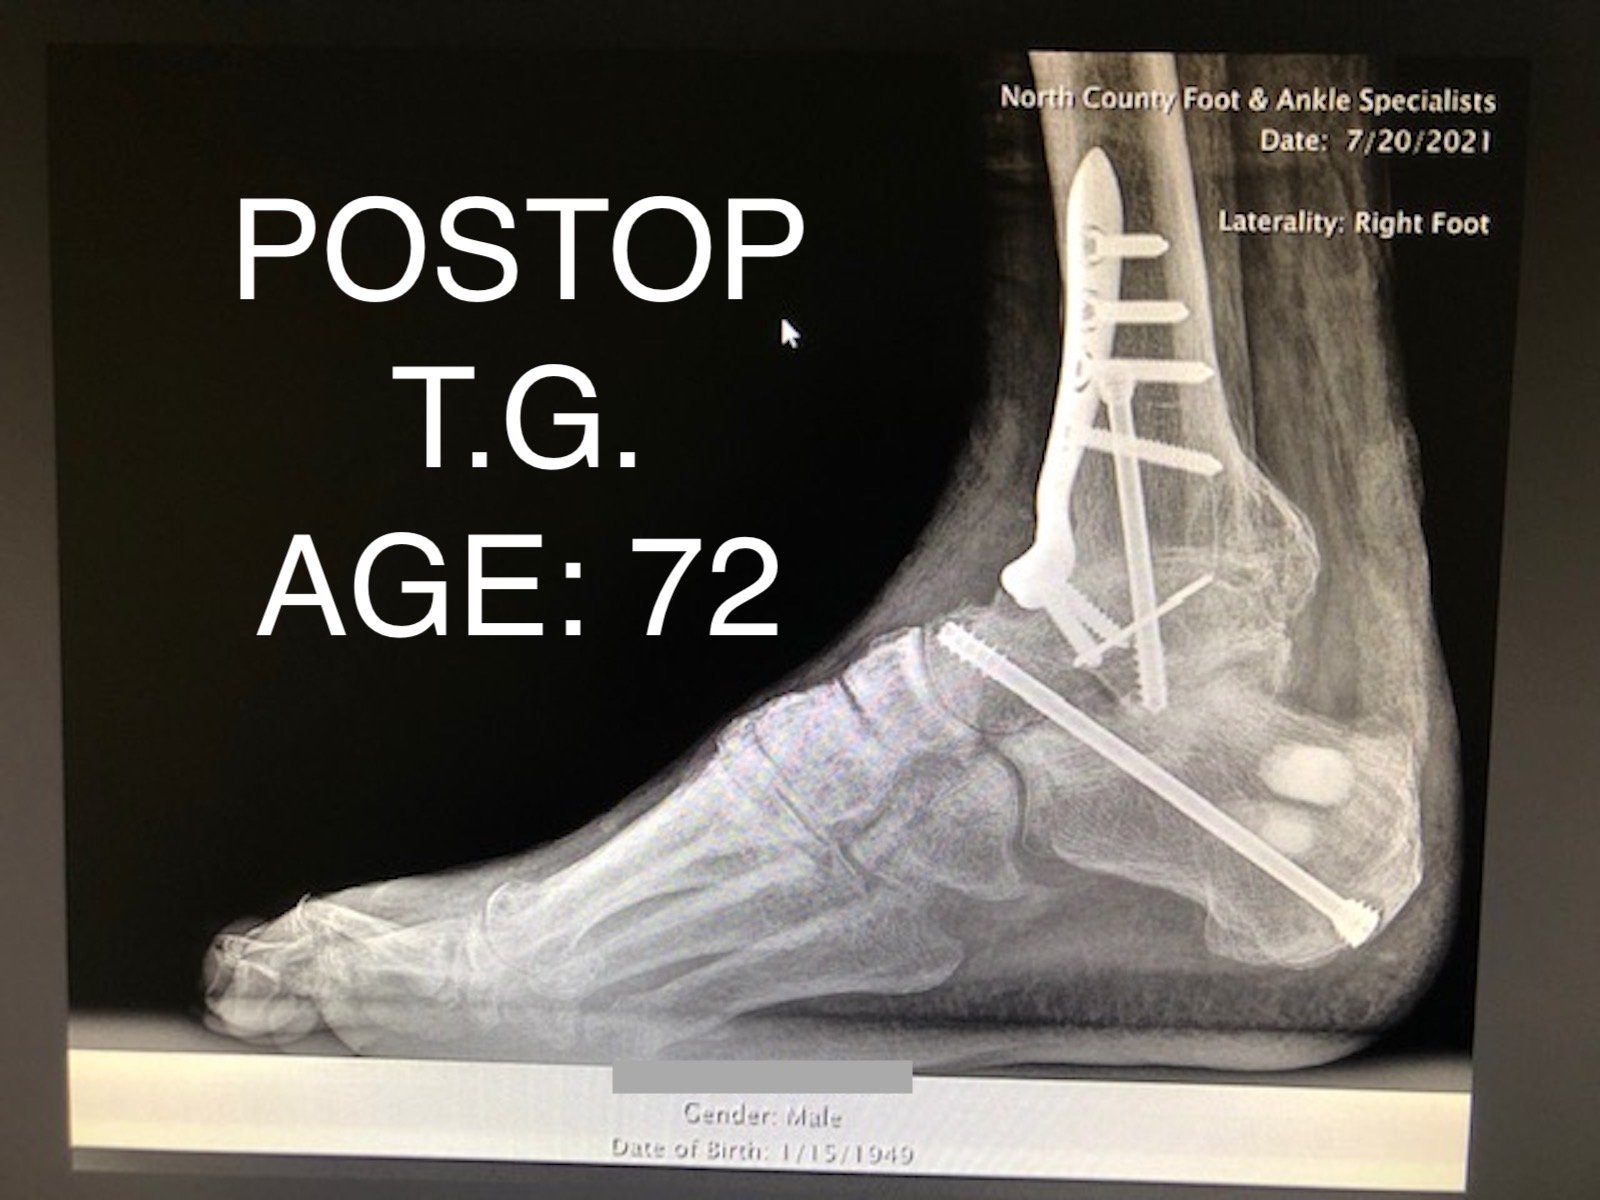

REAR FOOT FUSION